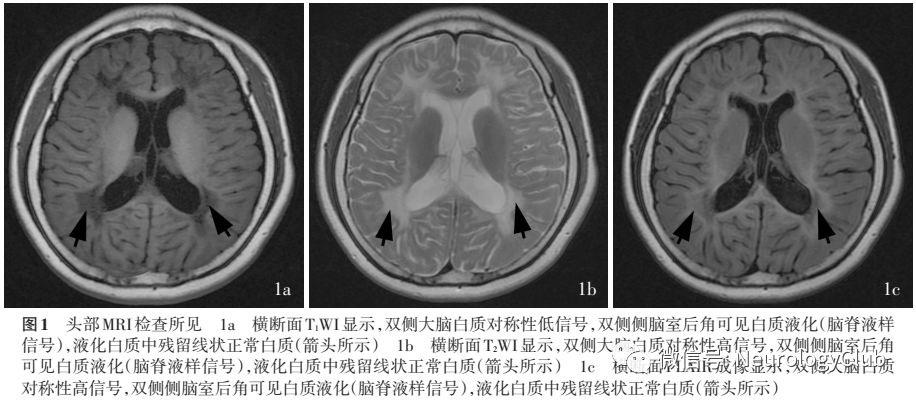

辅助检查  实验室检查:血尿便常规、血清脂质和肝肾功能试验、甲状腺功能试验、凝血功能、感染四项均于正常值范围;血清卵泡刺激素(FSH)为81.50IU/L(卵泡期5.10-7.00IU/L,排卵期4.90-16.40IU/L,黄体期2.50-5.10IU/L,绝经期15.90-54.00IU/L),雌二醇(E2)为24.52pmol/L(卵泡期183-565.10pmol/L,排卵期380.64-1683.60pmol/L,黄体期287.31-618.54pmol/L,绝经期0-201.67pmol/L),黄体生成素(LH)为23.19IU/L(卵泡期4.46-6.10IU/L,排卵期为8.80-49.70IU/L,黄体期2.60-5.70IU/L,绝经期为15.90-54.00IU/L),睾酮为0.32nmol/L(卵泡期0.89-1.48nmol/L,排卵期为1.26-1.91nmol/L,黄体期为1.05-1.80nmol/L,绝经期为0.21-0.91nmol/L),孕酮为0.48nmol/L(卵泡期为1.11-2.54nmol/L,排卵期2.19-9.83nmol/L,黄体期14.58-76.08nmol/L,绝经期0-2.31nmol/L,妊娠期>63.40nmol/L);胰岛素样生长因子-1(IGF-1)、皮质醇、促肾上腺皮质激素(ACTH)、血清氨、铜蓝蛋白(CP)、芳基硫酸酯酶A、α和β-半乳糖苷酶、半乳糖脑苷脂酶、氨基己糖苷酶A以及氨基己糖苷酶(A+B)均于正常值范围;TORCH[弓形虫(TOX)、风疹病毒(RV)、巨细胞病毒(CMV)、Ⅰ型和Ⅱ型单纯疱疹病毒(HSV-1和HSV-2)]、抗核抗体(ANA)谱19项均呈阴性;染色体核型:46,XX。腰椎穿刺脑脊液检查外观清亮、透明,压力115mmH2O(1mmH2O=9.81×10-3kPa,80-180mmH2O),蛋白定量490mg/L(150-450mg/L)、葡萄糖3.80mmol/L(2.30-4.10mmol/L)、氯化物123mmol/L(120-132mmol/L),髓鞘碱性蛋白(MBP)1.35nmol/L(≤0.55nmol/L),脑脊液细胞学未见异常,寡克隆区带(OB)阴性,TORCH以及抗N-甲基-D-天冬氨酸受体(NMDAR)、接触蛋白相关蛋白2(Caspr2)、α-氨基-3-羟基-5-甲基-4-异唑丙酸1和2受体(AMPA1R和AMPA2R)、富亮氨酸胶质瘤失活基因1(LGI1)、γ-氨基丁酸B型受体(GABABR)抗体均呈阴性。子宫和双附件超声显示,子宫较小,宫腔内少量积液。头部MRI检查显示,双侧大脑半球对称,双侧侧脑室旁和半卵圆区白质呈广泛性长T1、长T2信号影,侧脑室后角旁白质液化,胼胝体纤细(图1);磁共振波谱(MRS)无明显异常。神经电生理学检查:视频脑电图(VEEG)呈现以额叶显著的高波幅2-3Hzδ波和δ活动,两侧交替不对称,尤以左侧显著。基因检测:患者存在白质消融性脑白质病相关基因EIF2B5c.915G>A(p.Met305Ile)和c.1484A>G(p.Tyr495Cys)杂合突变(图2),均为已报道的致病性突变。

白质消融性白质脑病具有特征性影像学改变,对疾病诊断和进展评价具有重要价值。MRI表现为双侧大脑白质广泛性弥漫性对称性受累,脑白质呈液化样改变,早期液化白质中可见残留线状白质,晚期完全转变为脑脊液样信号